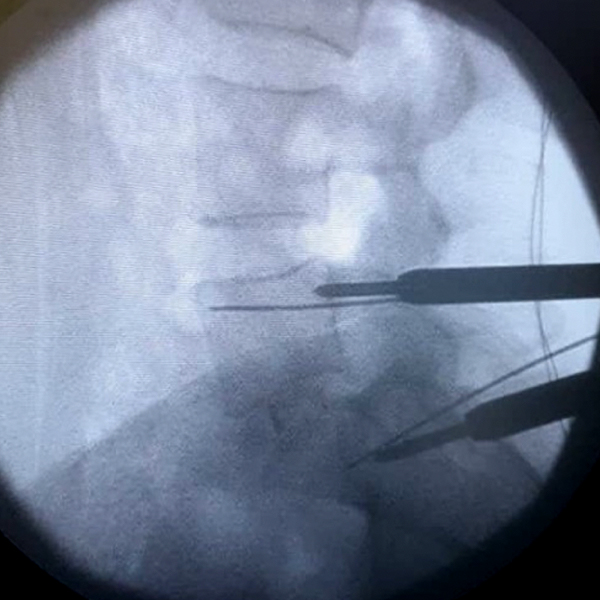

3. Colocación de los tornillos percutáneos:

Los tornillos se colocan en la parte posterior de la vértebra, de manera que el soporte entre dos vértebras está dada por la parte anterior por la caja intersomática y por la parte posterior por los tornillos. Se colocan dos tornillos por cada vértebra, uno derecho y otro izquierdo. Ellos se colocan a través de la piel por unos tubos especiales diseñados para ello a través de guías especiales que entran al pedículo. Estos tornillos se conectan finalmente por una barra longitudinal. Toda la colocación de los tornillos es viendo una cámara en vivo de Rx.